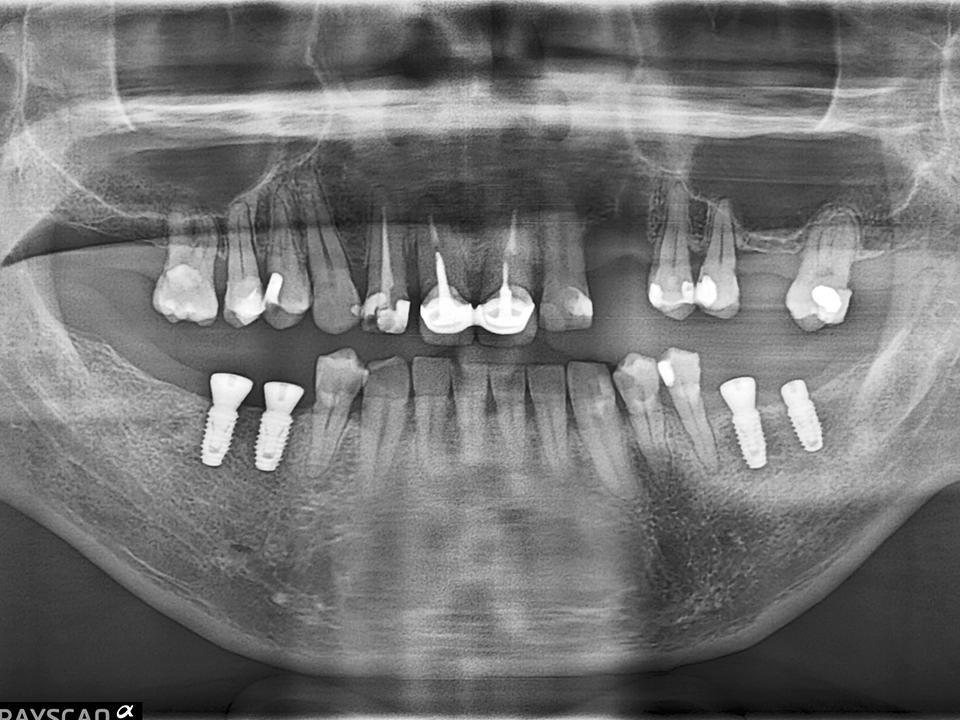

ALL ON全口重建

術式介紹

ALL ON全口重建是由4-6 顆植體(依條件而定)成,專為多顆缺牙或全口無牙患者設計的創新全口重建技術,僅需4-6 支植體即可支撐一整排固定式假牙,大幅減少手術次數與成本,並縮短療程時間。

All on 特點

適用無牙或重度牙周病患者

免補骨/少補骨即可植牙,降低手術複雜度

當天手術、當天裝牙,快速恢復日常功能